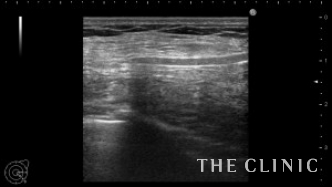

他院で4ヵ月前に脂肪による豊胸を行った方が、しこりで来院されました。

左胸に4㎝弱のしこりが触れ、エコーでは充実性のしこりでした。

壊死した脂肪が液状化したオイルシストであれば、注射針で吸引除去することが可能ですが、充実性の場合は吸引することは難しいです。